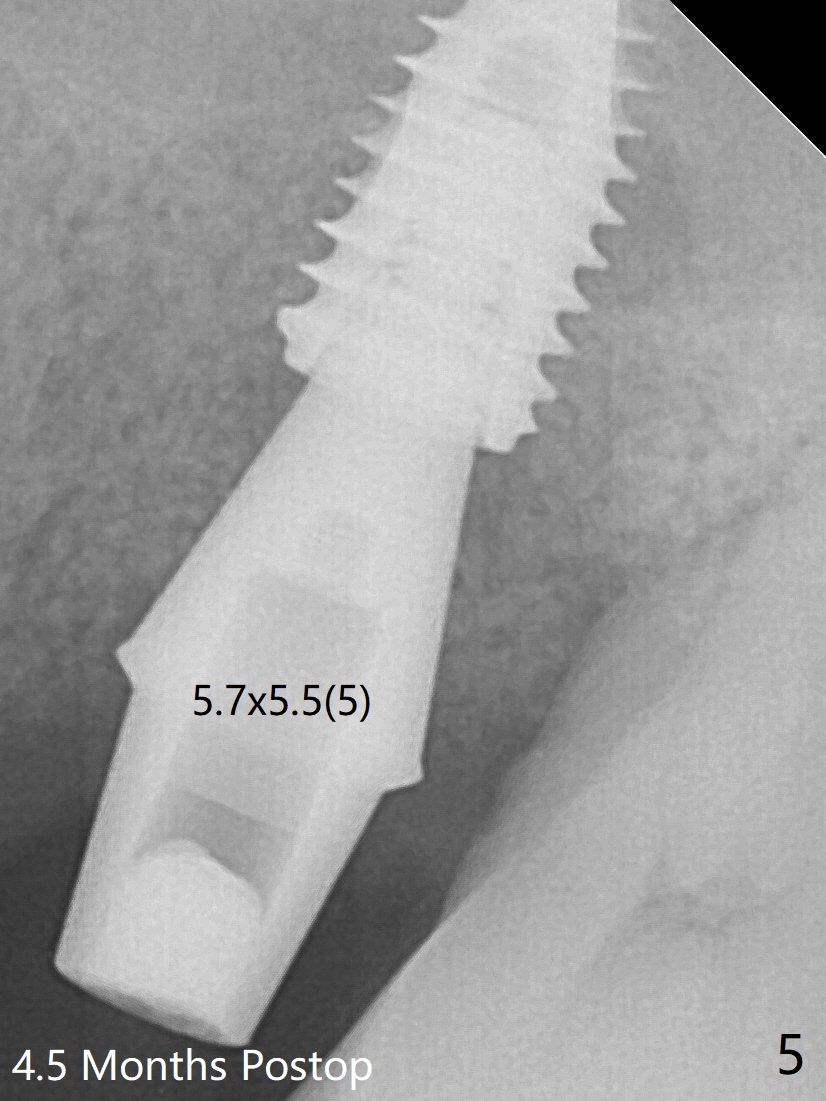

Six months post 2nd placement at #14, the 5x11 mm IBS implant is unstable. The patient smokes a cigarette a day.  After implant removal, the palatal wall of the osteotomy is intact, although low.  With removal of minimal granulation tissue, a 5x10 mm IS dummy implant is placed with stability and slightly subgingival palatal (Fig.1,2).  The abutment and implant are stable 4.5 months postop (Fig.5); a provisional is fabricated for progressive loading.